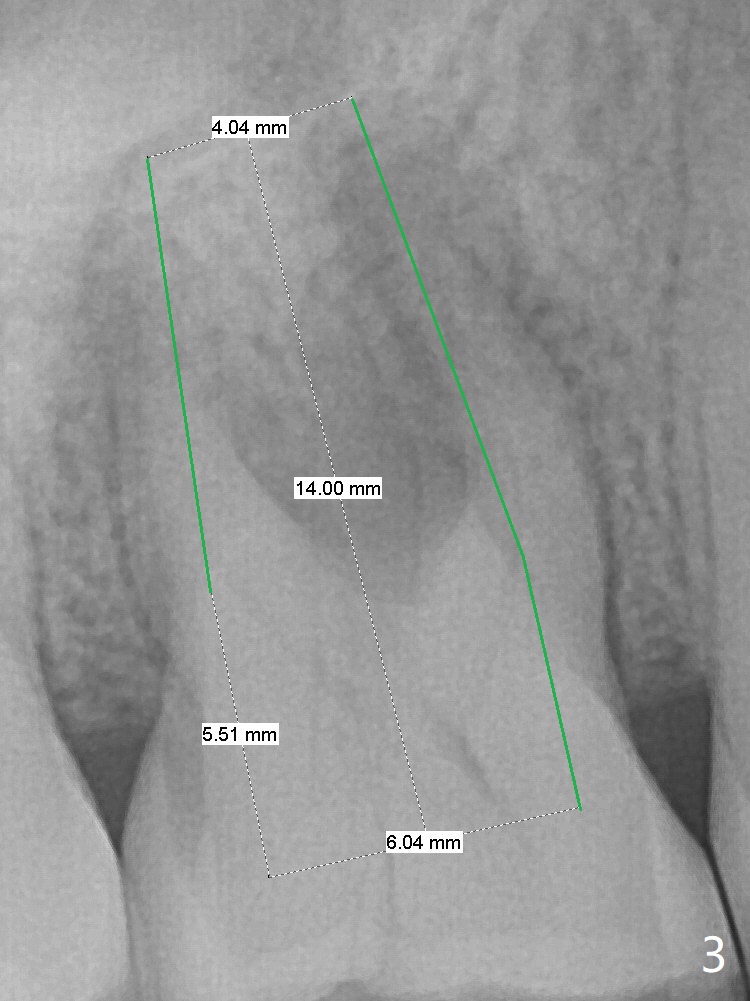

A 53-year-old woman has crack tooth symptom at #3 with apparently a vertical crack line on PA (Fig.1 arrow), suggesting bruxism. The latter may be easily associated with abutment screw loosening. To avoid this complication, a tissue-level implant will be placed (Fig.3). After extraction, the initial depth of osteotomy in the septum will be 7 mm (Fig.2). Find a pointed drill. Take preop photos to show the possible buccal crack line.